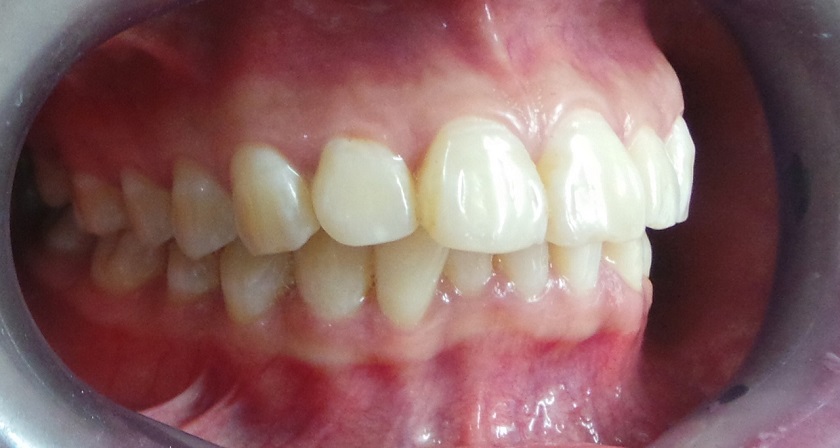

Hô hàm là một khiếm khuyết răng miệng dễ nhận biết. Bạn có thể thấy rõ tình trạng này khi răng hoặc xương hàm trên nhô ra phía trước quá mức so với hàm dưới. Khớp cắn bị lệch, khuôn mặt mất cân đối là những dấu hiệu điển hình.

Để xác định hô hàm có niềng răng được không, cần phân loại theo các dạng sau:

Hô do răng: Răng mọc chìa ra ngoài, không theo phương thẳng đứng.

Hô do xương: Xương hàm trên phát triển quá mức so với cấu trúc xương mặt, đẩy răng ra phía trước.

Hô do cả răng và xương: Trường hợp phức tạp, kết hợp cả hai yếu tố trên.